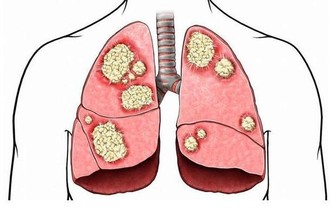

為何泡個腳就猝死 ?該醫院神經外科主任程新富介紹,經檢查發現,劉霞頭部腦血管有動脈瘤突發破裂。腦動脈瘤在未破裂前少有徵兆,很難發現,而一旦破裂,就會突發劇烈頭痛、意識障礙、噁心、嘔吐等癥狀,情況很兇險,致死、致殘率較高。少數特殊的腦血管動脈瘤會有眼瞼下垂、夜間頭痛、行走不穩等早期癥狀。

氣溫驟降時,腦血管疾病發病者明顯增加。劉霞發病時,正好遇到兩大誘因,一是天氣轉冷,二是深夜用熱水泡腳,都可能令血管受到強烈刺激,一定程度上誘發疾病。因此,有腦血管基礎性疾病的市民,近期應注意防寒保暖,避免身體遭受冷暖刺激。少用過熱的水洗澡、泡腳,少喝酒,避免情緒激動。同時,還應定時對身體進行全面檢查。